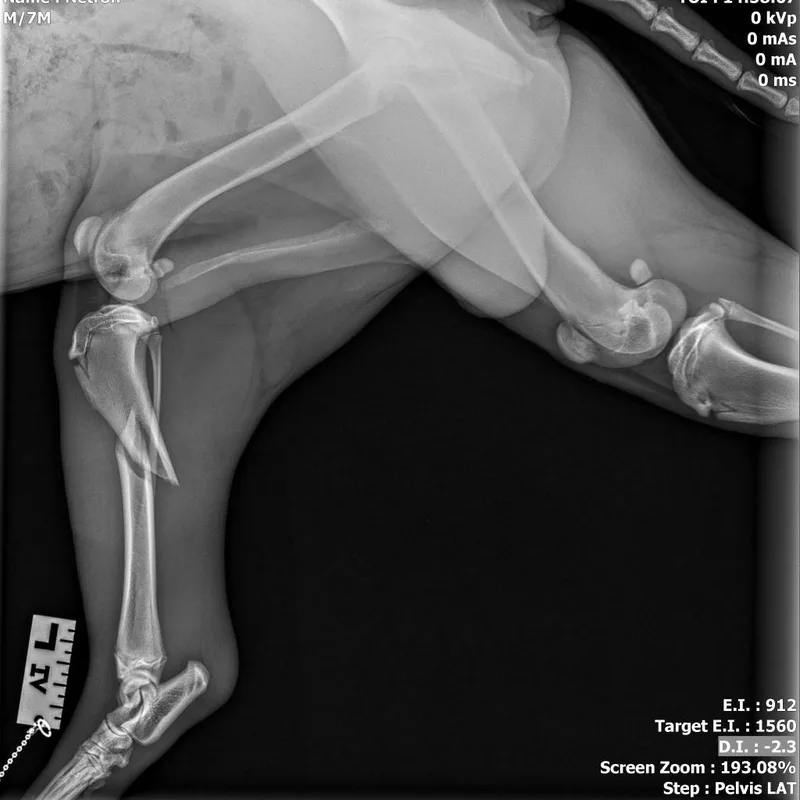

appears to have a displaced tibia fracture; this fx may be able to be set and splinted but will need to be set in alignment; x-rays have been reviewed by an off-site vet